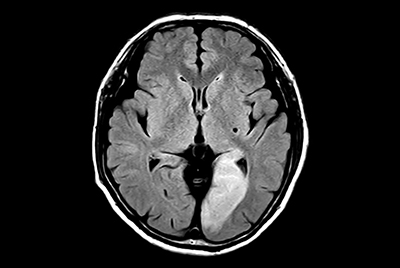

Brain - White matter lesions